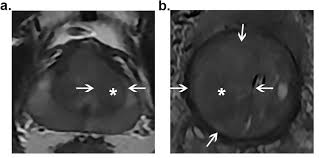

Https Epad Uroweb Org Wp Content Uploads 3 Role Of Mri J Barentsz Pdf

Https Epad Uroweb Org Wp Content Uploads 3 Role Of Mri J Barentsz Pdf from